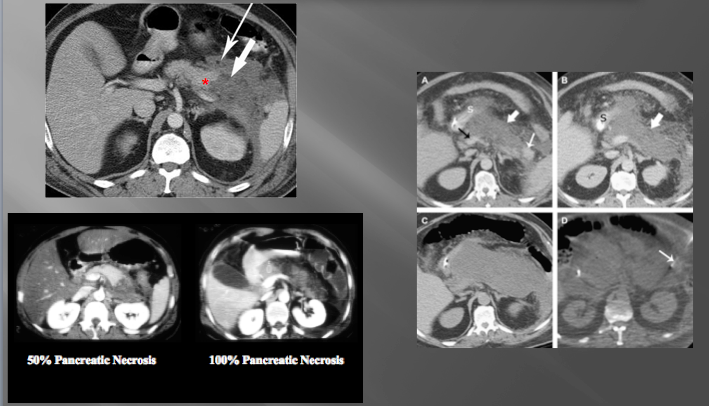

pancreatic necrosis